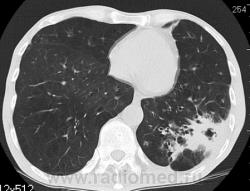

На фоне консолидации полость без содержимого. Может быть всё что угодно, что сопровождается деструкцией. Нужны ещё томограммы в лёгочном окне.

Изображения выставлены все. Ваше мнение уважаемые коллеги?

Туберкулёз.

Туберкулёз?

Это КТ 2-летней давности и попало оно мне в руки, после недавнего прохождения контроля пациентом, когда мы стали перед вопросом о специфическом / не специфическом процессе.

Тогда, пациента 2 месяца лечили от пневмонии, лечили интенсивности, стационарно, в серьёзном учреждении.

Предположу аспергиллез